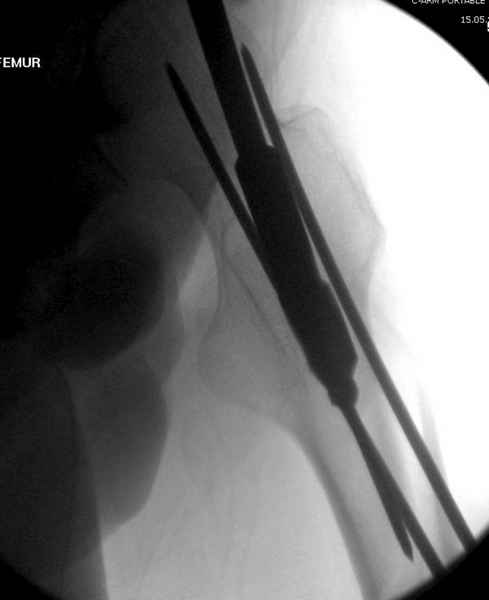

Среди русскоговорящих коллег Ортофорум стал одним из мест, где многие из нас черпают знания для решения своих ежедневных проблем в виде практических советов и обмена опытом. Кроме таких советов, Ортофорум стал источником новых познаний среди ортопедов, особенно по редко встречающимся состояниям в ортопедии. Продолжая традицию, я хотел бы представить редко встречающий случай перелома бедра у больного с гемофилией. Больному 42, гемофилия типа А, из истории упал с высоты около 1,5 метра, переправлен из другой больницы. По происхождению мексиканец, 10 лет назад по поводу артроза пр. коленного сустава в Мексике сделано протезирование, которое закончилось ампутацией выше коленного сустава. При поступлении бедро напряженное, сосудистых и неврологических расстройств нет. На рентгенограмме оскольчатый перелом бедра с вовлечением проксимальной спирали в шейку бедра. Хотели бы знать тактику ведения подобных больных и на что надо обратить внимание? Djoldas Kuldjanov, MD Department of Orthopedic Surgery St. Louis University Medical Center

Учитывая, что случай ургентный, больной поступил вечером, не стали делать вытяжение и срочно провели операцию по фиксации перелома бедра антеградным штифтом Versa Nail от DePuy.

Для профилактики дальнейшего раскола в шейке предварительно во время проксимального рассверливания спереди и сзади провели временные спицы, которые в дальнейшем были заменены на шурупы (miss nail method)